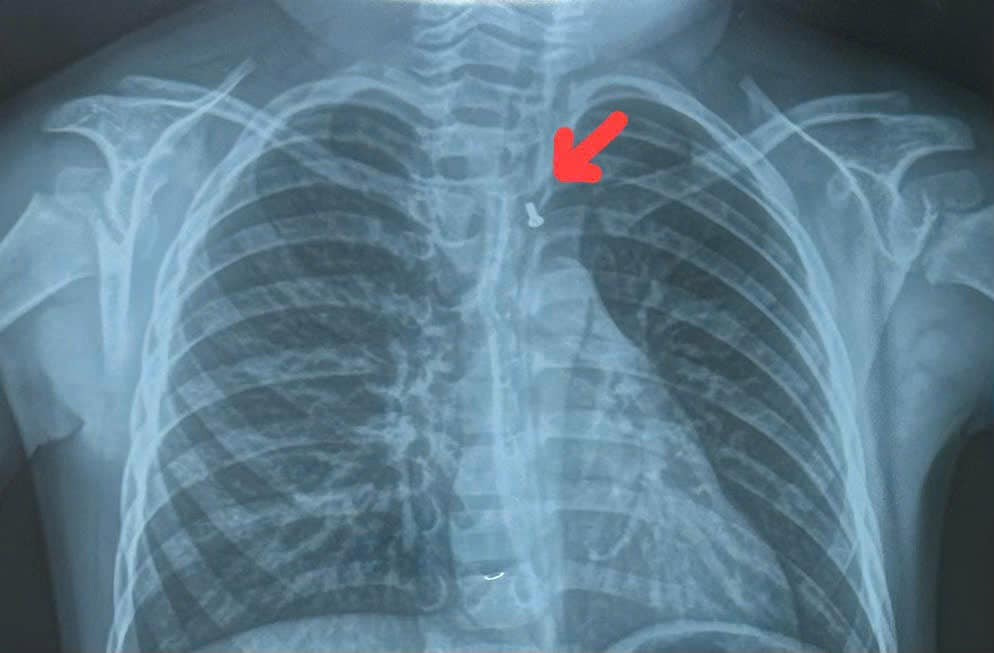

Bệnh nhi nhanh chóng được chuyển lên Bệnh viện Nhi Đồng 1 với chẩn đoán hóc dị vật. Qua kiểm tra, bác sĩ phát hiện, dị vật có hình con cá với nhiều cạnh sắc nhọn đang nằm trong thực quản bệnh nhi. Sau hội chẩn, bệnh nhi đã được bác sĩ chỉ định nội soi lấy dị vật.

| Hình ảnh con cá đồ chơi bị kẹt lại trong thực quản khiến bệnh nhi không thể ăn uống được |

BS Hoàng Vinh cho biết, trong quá trình nội soi, hình ảnh trên camera cho thấy dị vật là con cá nhựa dài khoảng 2cm, có nguy cơ gây tổn thương thực quản của trẻ. Ê kíp nội soi đã gắp thành công dị vật ra ngoài. Bệnh nhi may mắn khi không bị tổn thương thực quản. Sau khi lấy được dị vật, sức khỏe của trẻ đang bình phục tốt.